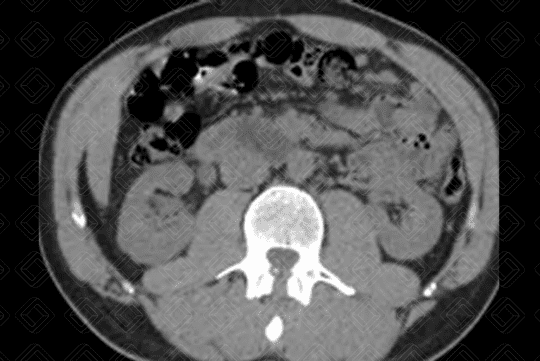

Texto alternativo para a imagem Figuras 1, 2 e 3. Créditos: Elazir Mota - Rio de Janeiro/RJ

Descrição das figuras 1, 2 e 3: Tomografia computadorizada sem contraste do abdome evidenciando cálculo (setas brancas) no terço médio do ureter direito, medindo cerca de 0,4 cm e com densidade de 723 UH (é importante fornecer a densidade do cálculo para inferirmos a composição do mesmo). Observa-se ainda pequena dilatação do ureter a montante (seta vermelha).

• Tomografia computadorizada do abdome total: Tomografia computadorizada do abdome sem contraste é o exame de escolha para avaliação de cálculo ureteral em adultos e idosos;